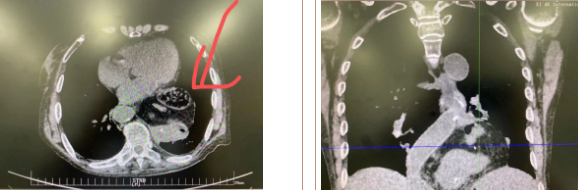

經(jīng)過(guò)三周充分準(zhǔn)備、院內(nèi)多學(xué)科會(huì)診及嚴(yán)謹(jǐn)?shù)男g(shù)前討論,西安國(guó)際醫(yī)學(xué)中心醫(yī)院胸科醫(yī)院李文海副院長(zhǎng)帶領(lǐng)團(tuán)隊(duì)為一位82歲高齡,多臟器功能不全且合并腫瘤患者成功實(shí)施“巨大膈疝修補(bǔ) 抗返流手術(shù)”。

據(jù)了解,患者多年來(lái)進(jìn)食后出現(xiàn)惡心、嘔吐,卻未到醫(yī)院進(jìn)行檢查。3個(gè)月前患者突然出現(xiàn)無(wú)尿,全身腫脹等情況才前往就醫(yī),卻遭多家醫(yī)院拒收,輾轉(zhuǎn)來(lái)到我院就診。檢查發(fā)現(xiàn)患者已患宮頸癌、進(jìn)而引起腎后性腎衰、同時(shí)合并膈疝、出現(xiàn)泌尿道感染,病情及其復(fù)雜。

經(jīng)泌尿外科積極救治,患者腎衰癥狀緩解,隨后轉(zhuǎn)入放射治療中心進(jìn)行宮頸癌根治性放療。放療期間,患者惡心、嘔吐癥狀逐漸加重,后期無(wú)法進(jìn)食,排除機(jī)械性腸梗阻和放療因素,考慮因長(zhǎng)期膈疝加重引起,經(jīng)胸外科會(huì)診后轉(zhuǎn)入胸外科一病區(qū)準(zhǔn)備手術(shù)治療。

麻醉手術(shù)中心副主任丁倩為減輕患者術(shù)后不適,實(shí)施單腔聯(lián)合支氣管封堵插管,同時(shí)進(jìn)行了肋間神經(jīng)阻滯麻醉。術(shù)中發(fā)現(xiàn)患者膈疝巨大,食管和疝囊分界不清,部分胃組織和結(jié)腸疝已進(jìn)入胸腔。李文海憑借豐富的臨床經(jīng)驗(yàn),仔細(xì)辨別解剖變異,有序完成分離、縫合、修補(bǔ)等一系列操作,胸外科穆強(qiáng)副主任醫(yī)師、劉歡住院醫(yī)師、麻醉手術(shù)中心團(tuán)隊(duì)通力配合,手術(shù)最終順利完成,患者安全返回胸外科監(jiān)護(hù)室病房。目前患者術(shù)后恢復(fù)良好,于近日準(zhǔn)備出院。